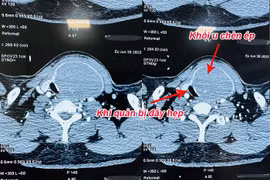

Người bệnh bị bướu cổ hơn 30 năm với kích thước khối u tuyến giáp lớn, chèn ép, đẩy khí quản cổ sang một bên gây khó thở đã được các bác sỹ Bệnh viện Nhân dân Gia Định phẫu thuật thành công.

Bị u tuyến giáp lành tính to không mổ, đến khi nuốt vướng mới đến lại bệnh viện thì u vỡ, chèn ép khí quản, thần kinh thanh quản và thực quản gây nguy hiểm tới tính mạng.

Các bác sĩ Bệnh viện TWQĐ 108 vừa phẫu thuật thành công khối u tuyến giáp khổng lồ với kích thước thùy phải 10x6cm, kích thước thùy trái 12x7cm, phát triển cả lên phía trên và đẩy xuống nền cổ, gây đè hẹp khí quản.